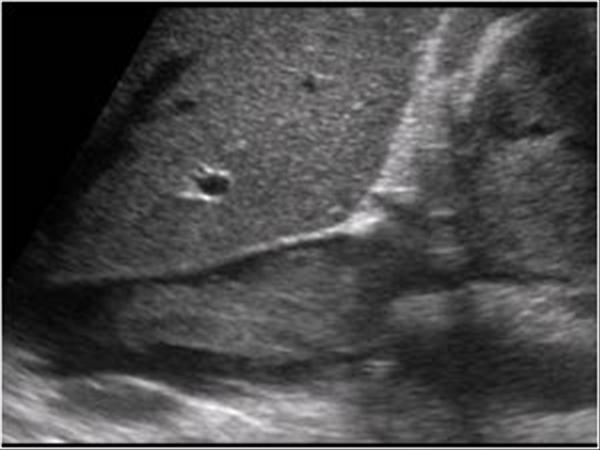

RCC

» Thông tin: Nữ giới – 69 tuổi.

» Lâm sàng: Đái máu.

# Ung thư biểu mô tế bào thận phải (Renal cell carcinoma – RCC) / Huyết khối tĩnh mạch chủ dưới.